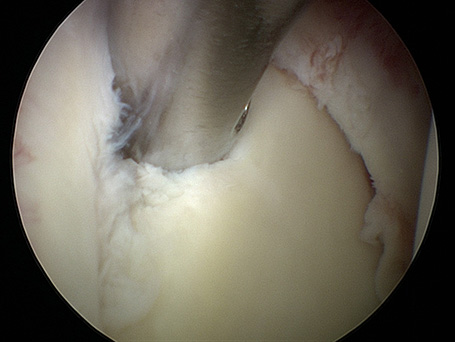

Junger Patient mit dorsaler Instabilität nach vorangegangenem Trauma und dorsalem knöchernem Pfannenrandabbruch. Intraoperativ bereits völlig fest verheiltes Knochenfragment. Stabilisation mit Reschspan über arthroskopisch gestützte Technik mit funktionell unauffälligem schmerzfreiem klinischen Ergebnis .

DORSALE SCHULTERINSTABILITÄT KNÖCHERN

Postoperatives Bild nach 6 Monaten: Span dorsal eingeheilt